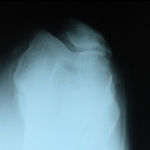

A 62 year old, female patient presented with a history of increasing right knee pain and loss of function over a 3-year period.

On clinical and radiological examination, she was assessed as having Medial Compartment Osteoarthritis. A uni-compartmental knee replacement was recommended and performed in June 2011. Patient has gone onto complete recovery with a satisfactory clinical outcome. She returned to independent function, six weeks after the surgery and now has a pain-free existence with full function in the right knee.